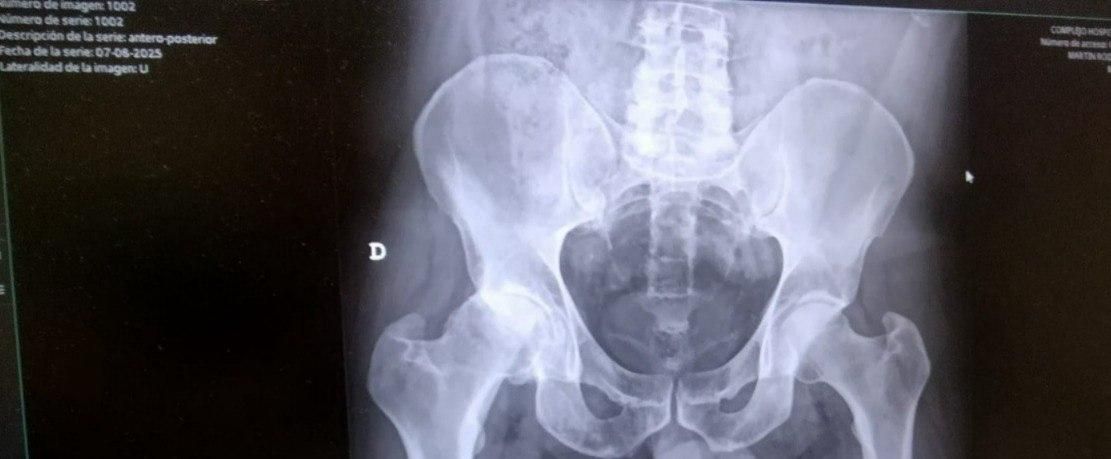

Radiografía que muestra la coxartrosis severa de cadera derecha (izquierda en la imagen) de Pedro en agosto de 2025.

Su diagnóstico: coxartrosis severa de cadera derecha. Se trata de un desgaste del cartílago en la articulación de la cadera y que además de dolor provoca limitación de movimiento, teniendo que ser necesaria una intervención quirúrgica para reemplazarla. En su informe médico se señala que se encuentra “clínicamente muy mal, muy limitado”, según detalla su traumatóloga.